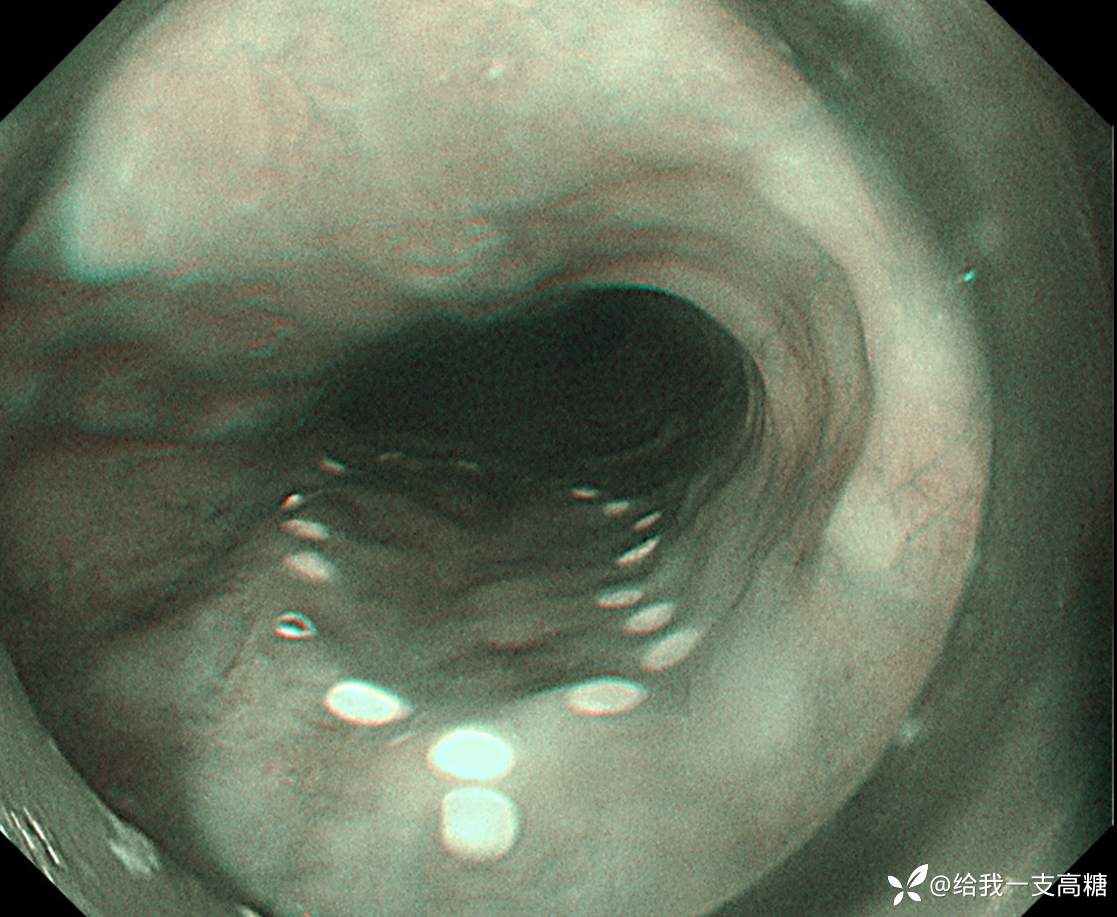

标记,口侧双标

完整剥离、固定